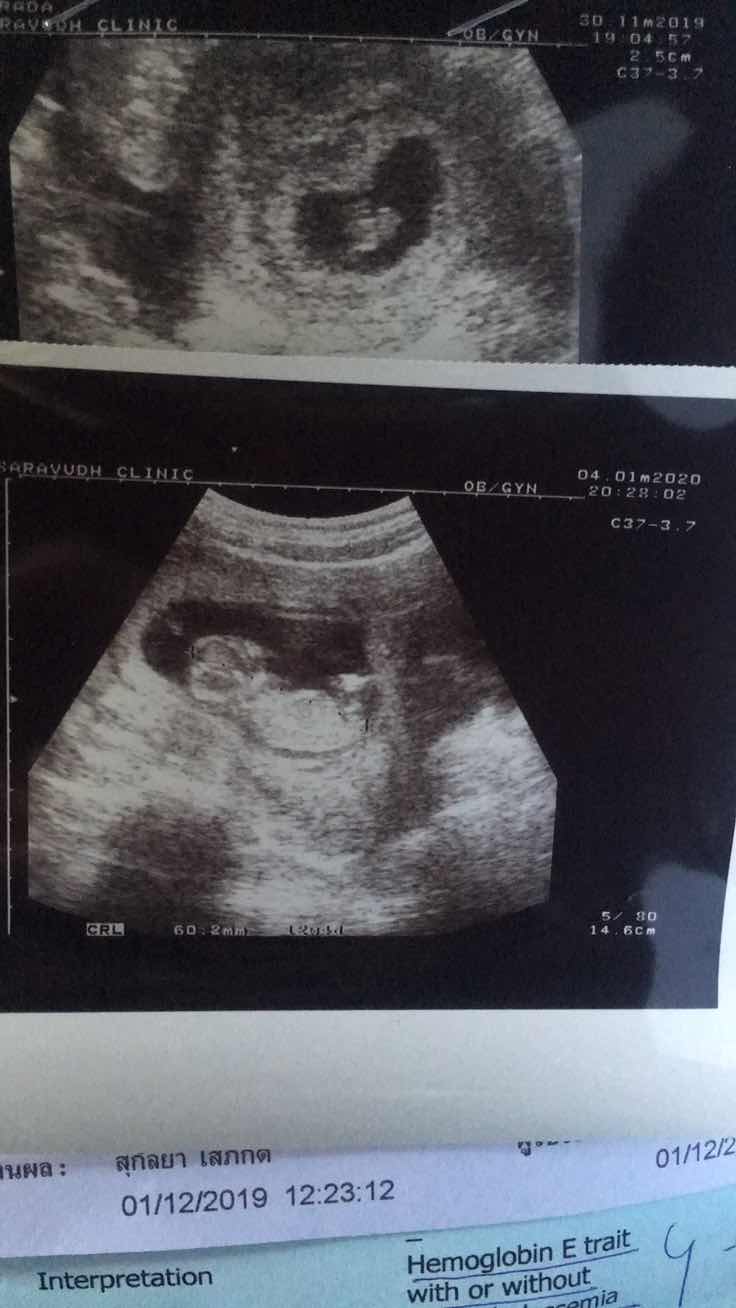

3เดือนจ้า

ภาพแรก7week 6day.